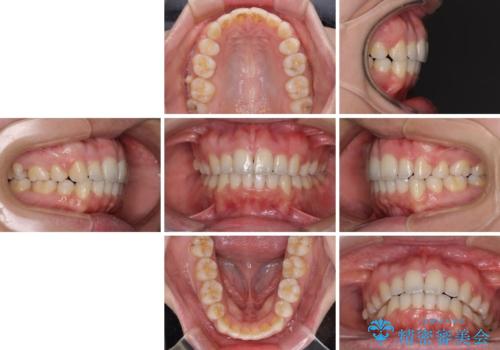

- 前歯のデコボコと口元の突出感を気にして来院された患者様です。

上下左右第一小臼歯4本を抜歯し、ワイヤー装置にて口元を引っ込めるよう矯正治療を行うこととしました。

叢生が強かったため、口元の突出感の改善には限界がありましたが、横側からも口元が引っ込んだ感じが分かるほど改善されました。